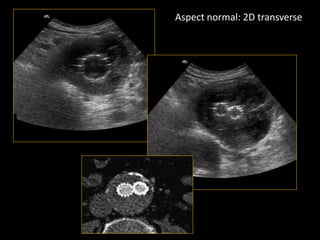

Aspect normal: 2D transverse

Coupes 2D transverses étagées

• incidence perpendiculaire à l’axe aortique

section circulaire

• mesure du diamètre antéropostérieur externe

maximal, moyenne de 3 mesures